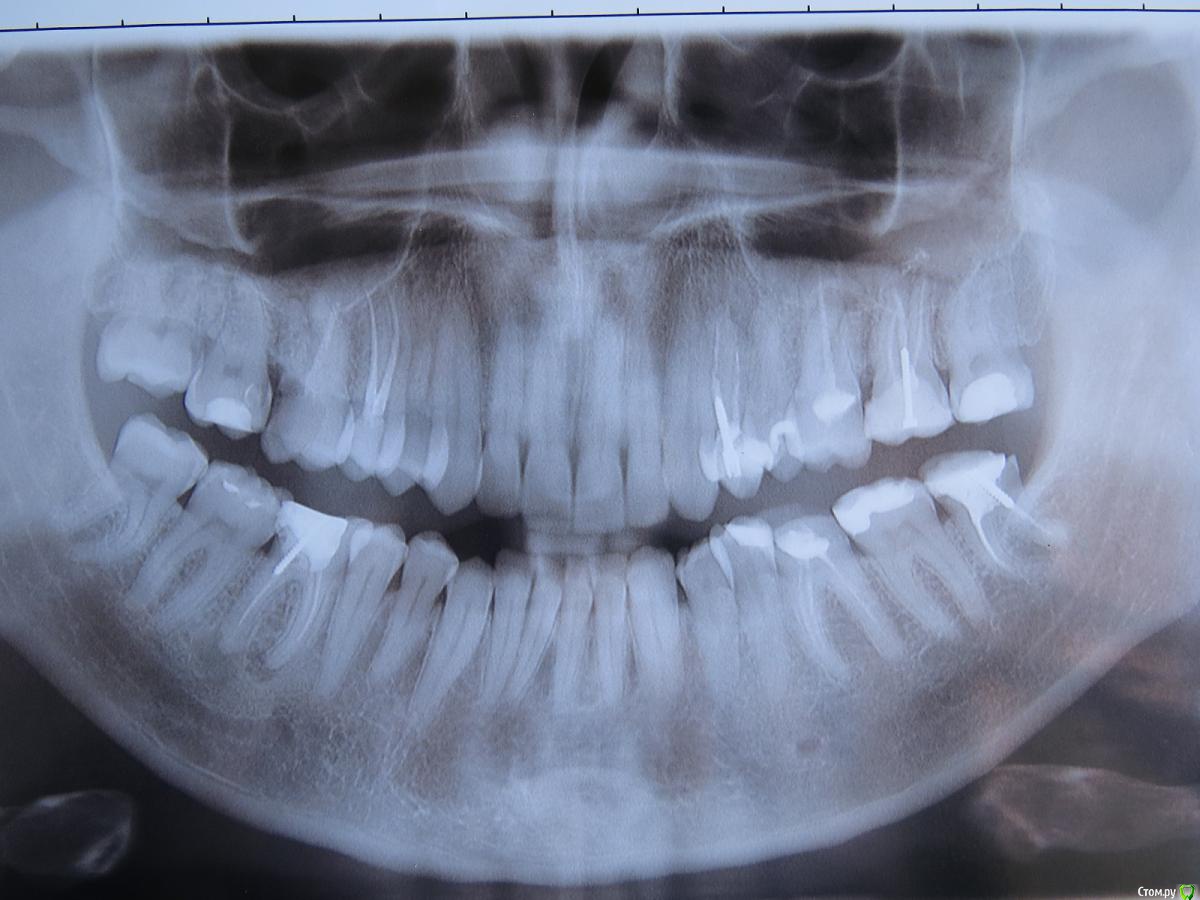

Решил заняться своими зубами поплотнее и комплексно после того, как делал у стоматолога-терапевта очередной отколовшийся зуб и врач мне сказал, что мне надо бы окклюзию восстановить и желательно делать все зубы в комплексе, но он за это не возьмется, т.к. это очень сложно для него. Про окклюзию до этого случая я не задумывался..

На данный момент (33 года, муж.) имею следующие проблемы.

1. Все шестерки и семерки надо переделывать. Где-то сделано как пенек, где-то пломба (еще во время учебы в школе делалась) просела, где-то коронку надо.

2. В суставе справа щелчков не наблюдается, но как-то неуютно ему. Хочется как-то им подвигать, поразминать порой, думаю что ему или мышцам не нравится сложившийся прикус.

3. Прикус мой сидит на резцах, клыках и 4-х при этом боковые зубы (6,7,8) по ощущениям не смыкаются или смыкаются очень слабо, причем справа ситуация со смыканием боковых хуже чем слева. Резцы, клыки и 4-ки интактны, кроме 24.

1. Пользуясь ситуацией, что все зубы (боковые) надо делать, хочу поднять окклюзионную высоту с боков, убрать имеющиеся суперконтакты (по ощущениям это клыки). Все, в конечном итоге, для того, чтобы прикус был удобным.